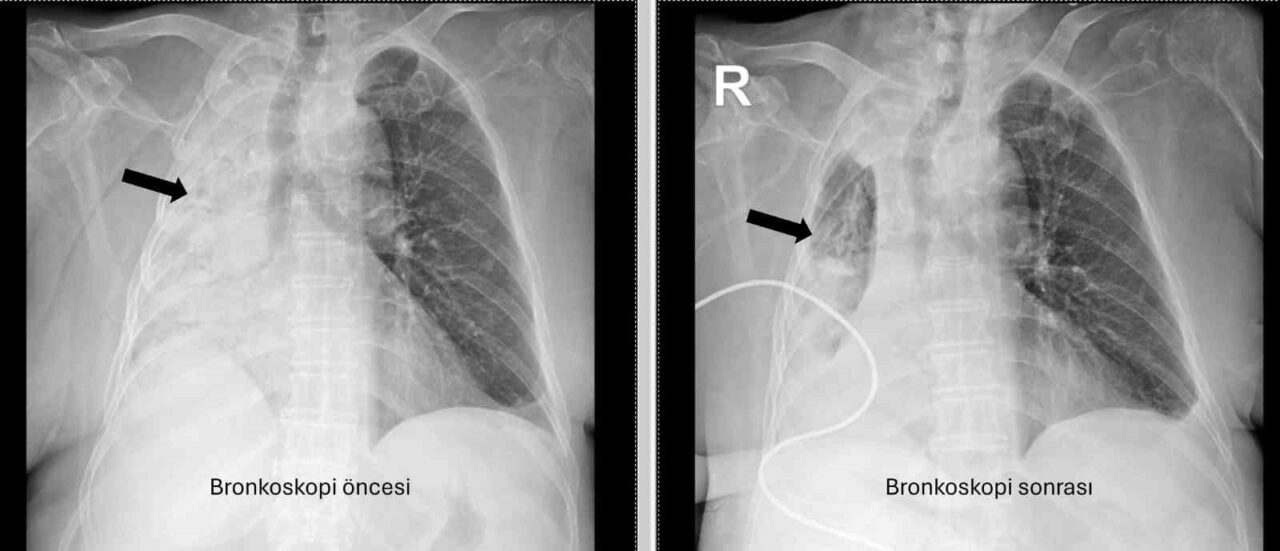

Denizli’de yaşayan ve emekli öğretmen olan 78 yaşındaki felçli kadın son zamanlarda sık sık akciğer enfeksiyonu nedeniyle hastaneye gidiyordu. 1 ay önce gittiği hastanede bronkoskopi yapılmasına rağmen sorun saptanmadığı öğrenildi. Yaşlı kadının son gittiği hastanede sağ akciğerinin tamamen kapandığının tespit edilmesi üzerine Pamukkale Üniversitesi Hastanesine başvuruldu. PAÜ Hastaneleri Göğüs Hastalıkları Anabilim Dalı Öğr. Üyesi Prof. Dr. Göksel Altınışık Ergur, tarafından yapılan tetkiklerde sağ akciğere giden hava yolunun bütünüyle kapalı olduğu görüldü. hastaya acil bronkoskopi planlanıp hemen işlemin gerçekleştirildiğini söyleyen Prof. Dr. Altınışık Ergur, “Fleksibl (esnek, eğilip bükülebilir) bronkoskop ile hava yolları incelenirken çok yoğun ve koyu sekresyon olduğu, bunun iyice temizlenmesi sonucunda ancak hava yollarının incelenebileceği görüldü. Aspiratör (içerideki salgıları emmeye yarayan bir cihaz) sayesinde hava yollarına steril sıvı verilip emilerek bu temizlik yapıldı. Sonrasında sağ akciğere giden hava yolunda sarı bir nesne olduğu görüldü. Bu hâliyle yabancı cisim olduğu anlaşıldığı gibi bunun mısır tanesine benzerliği de açıktı. Yabancı cismi çıkarma işlemi genel anestezi altında, rijit bronkoskop ile yapılmak üzere planlanabilirdi; çünkü bu durumun tedavisi yabancı cismin oradan, ek sorun oluşturmaksızın çıkarmaktı. Ancak, genel anestezi altındaki bir işlem için hastanın genel durumu bozuk olduğundan, özellikle ek hastalıkları ve enfeksiyon varlığı ile işlem riski artacağından hastadaki cismin fark edildiği sırada çıkarılmasına şans vermek daha uygun görüldü. Hava yolu içindeki sıvıları emen aspiratörün gücünü kullanılarak cismin çıkarılması mümkündü. Bronkoskobun ucu, sarı cismin gövdesine dayanıp aspiratör ile emme sayesinde ikisi birbirine sımsıkı yapıştırıldı. Emme gücünün azaltılmamasına dikkat ederek yabancı cisim ve bronkoskop, aynı zamanda hava yollarından dışarıya başarı ile çıkarıldı. İşlem sonrasında hasta yakınına mısır tanesi açısından tıbbi öykü yeniden sorulduğunda, hastamızın bundan beş ay önce yediği pizzanın üzerinde mısır taneleri olduğu öğrenildi. O sırada ani bir yakınma ortaya çıkmadığı için böyle bir ihtimal akla gelmemişti. Düşkün hastalar taneli gıdalar yerken, bu durumun fark edilmeden de gelişebileceğini göstermesi açısından önemli olan bu tablo, hastaların bir dedektif titizliği ile değerlendirilmesi gerekliliğini bir kez daha ortaya koymaktadır” dedi.